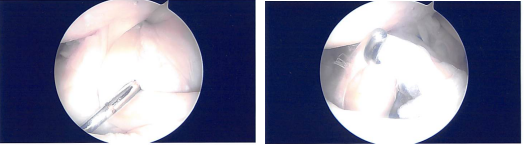

The patient was taken to the operating room where she was placed on a well-padded operating room table. Left lower extremity was prepped and draped aseptically. A time-out was called. Preoperative antibiotics were given. Tourniquet was Inflated.

Lateral entry portal was made and the scope entered. There was ____ In the patella as well as on the medial femoral condyle which after making a medial portal, cleaned arthroscopically using a shaver.

Examination of the medial meniscus showed a tear of the anterior horn of the medial meniscus which was clean. The intercondylar notch showed an intact ACL. Lateral tibiofemoral compartment examination was normal.

After thorough Irrigation, final pictures were saved and the wound was closed. Then, 40 mg of Depo-Medrol was injected in the left knee after the surgery.